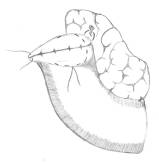

Больной П., 61 года, 21.02.2011 поступил в терапевтическую клинику с жалобами на похудение, общую слабость. 25 лет страдал язвенной болезнью, язвой ДПК, преимущественно залуковичной локализации, систематически лечился у гастроэнтерологов. При ФГДС обнаружена рубцовая деформация луковицы ДПК; КТ – конкременты желчного пузыря, аэробилия; рентгеноскопии желудка и дуоденографии – контрастирование вне- и внутрипеченочных желчных протоков и желчного пузыря, рубцовая деформация постбульбарного отдела ДПК (рис. 1).